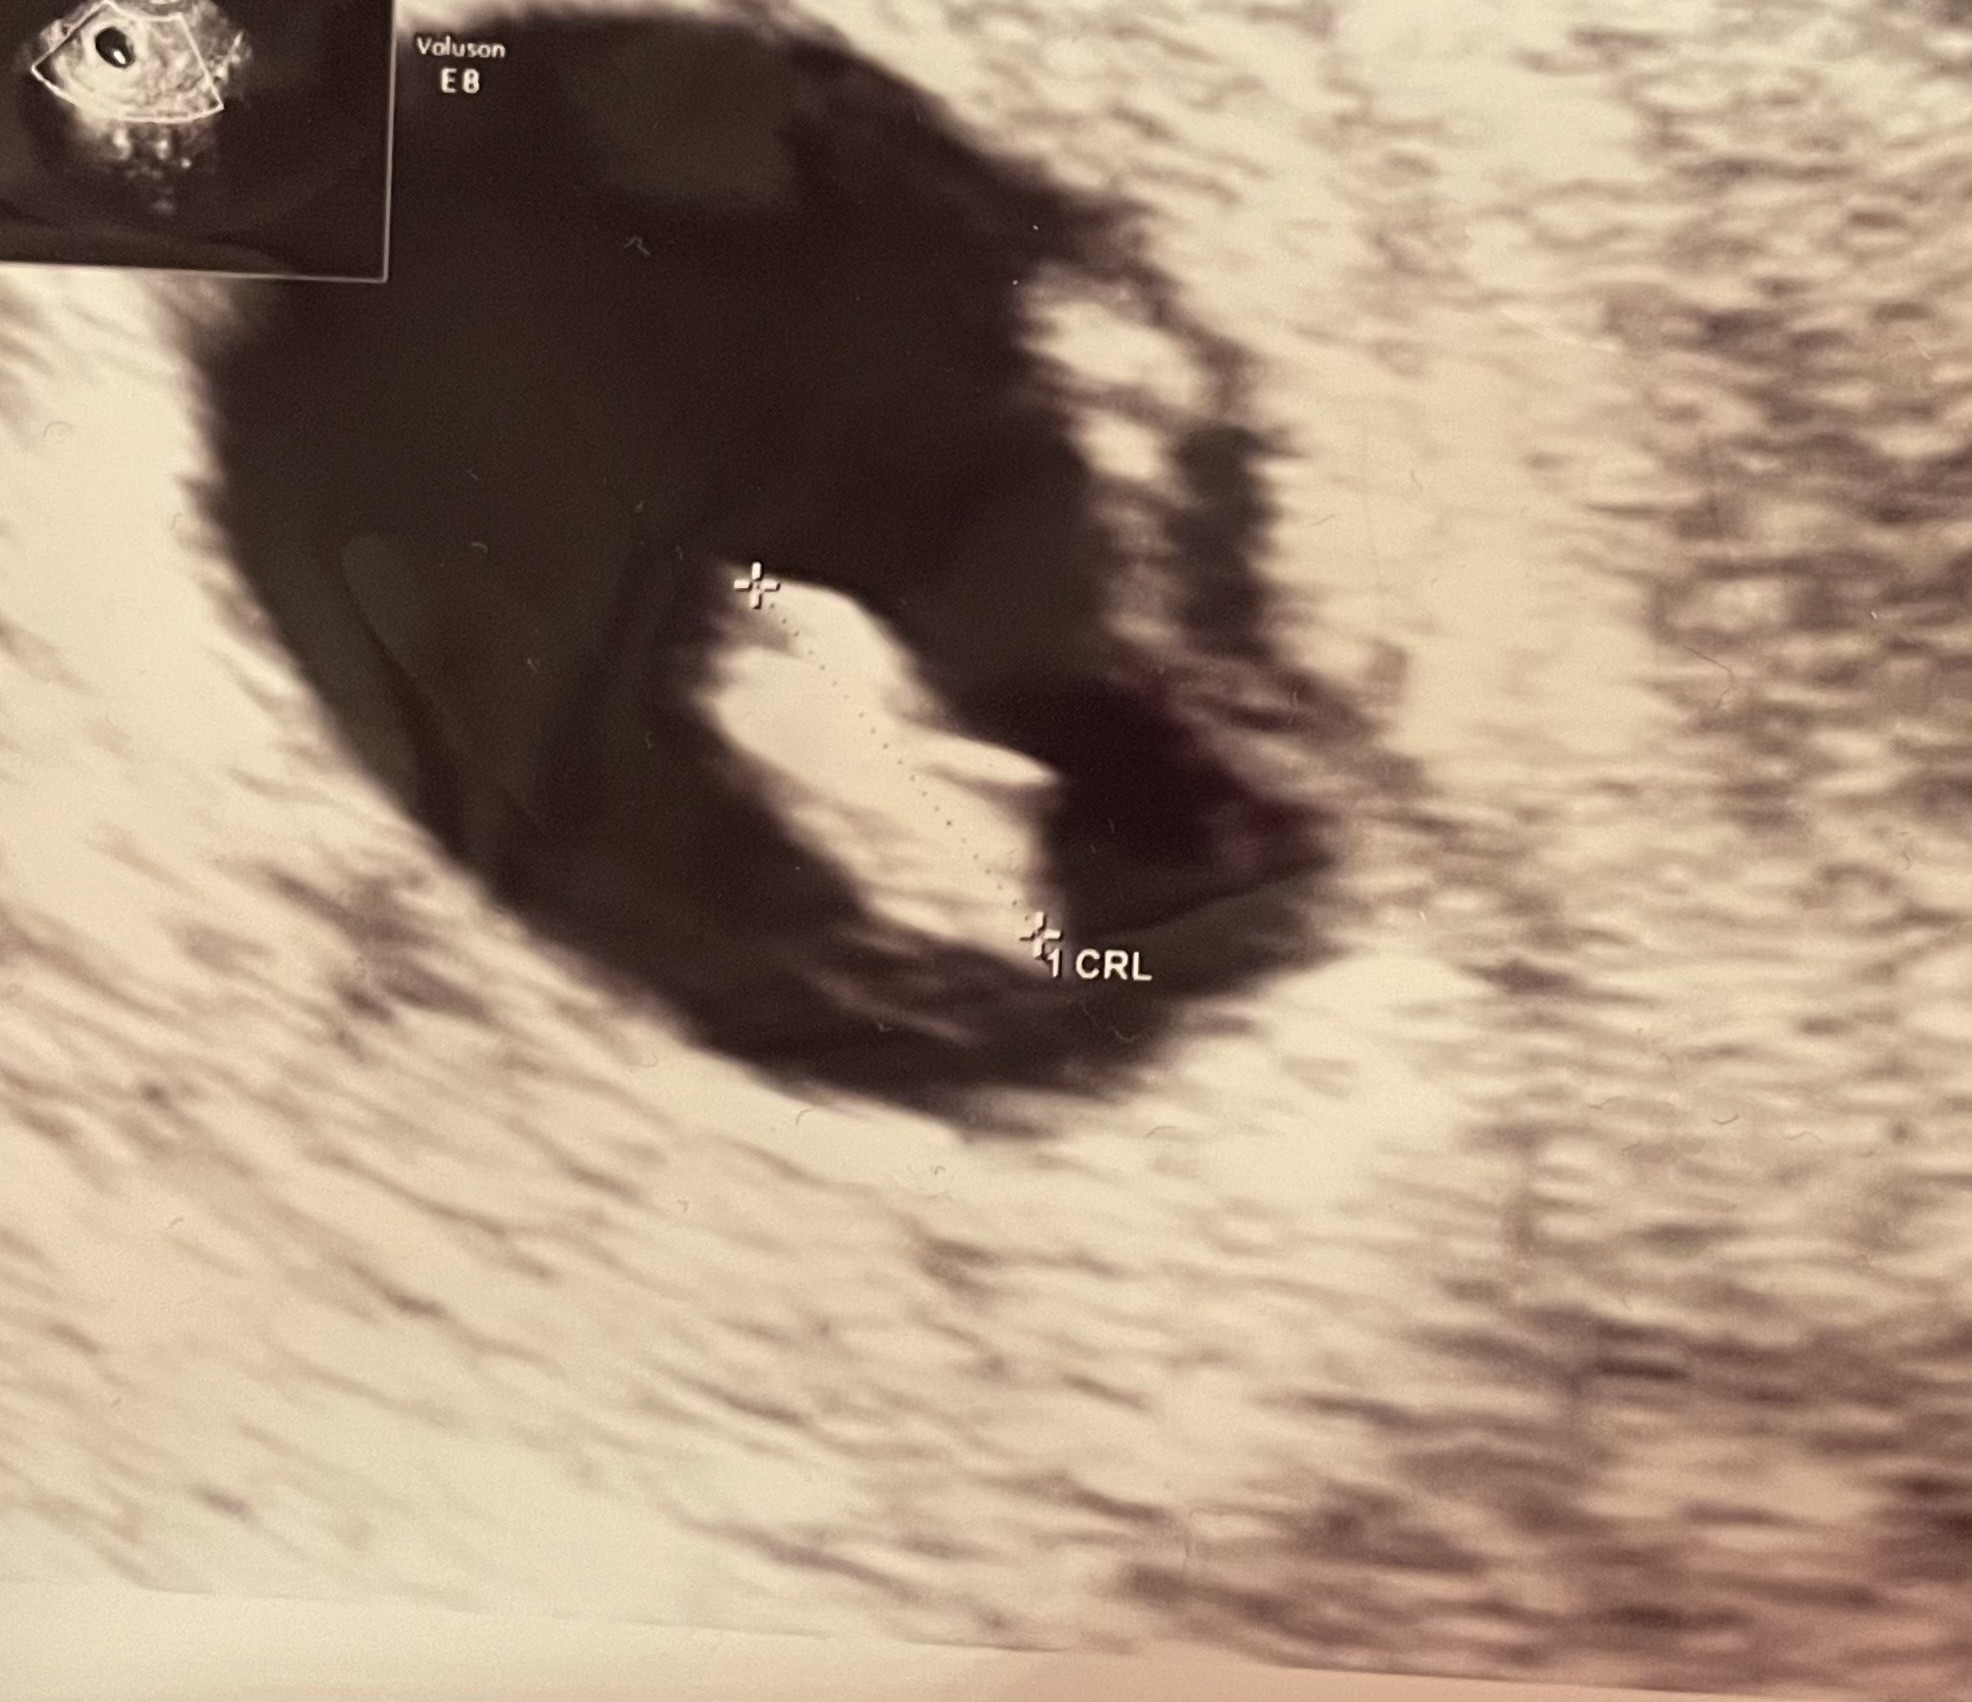

bo ja badałam tylko 2x do poziomu kilkuset, później uważam że nie ma sensu i przyrost ponad 200%, miałam też dużego proga i przez chwilę myślałam że bliźniaki, ale jednak usg nie potwierdziło

A po co badałaś betę tego samego dnia jak już widziałaś serduszko i wszystko było ok? Przy takich wartościach (i już po potwierdzonym usg!!) już się nie powinno badać bety bo później właśnie jest stres, płacz i zgrzytanie zębów. Tak jak Lea pisała, wzrost już nie będzie powyżej 66%, a na tym etapie już tylko usg jest rozstrzygające bo beta już Ci nic nie powie. Ja w poprzedniej ciąży badałam przy okazji innych badań, bo coś było nie tak i miałam bete chyba 14tys,a i tak później się okazało że zarodek prawdopodobnie zatrzymał się na 5tyg. Także beta akurat nic nie wniosła. Ty musisz teraz czekać do kolejnej wizyty żeby się uspokoić.